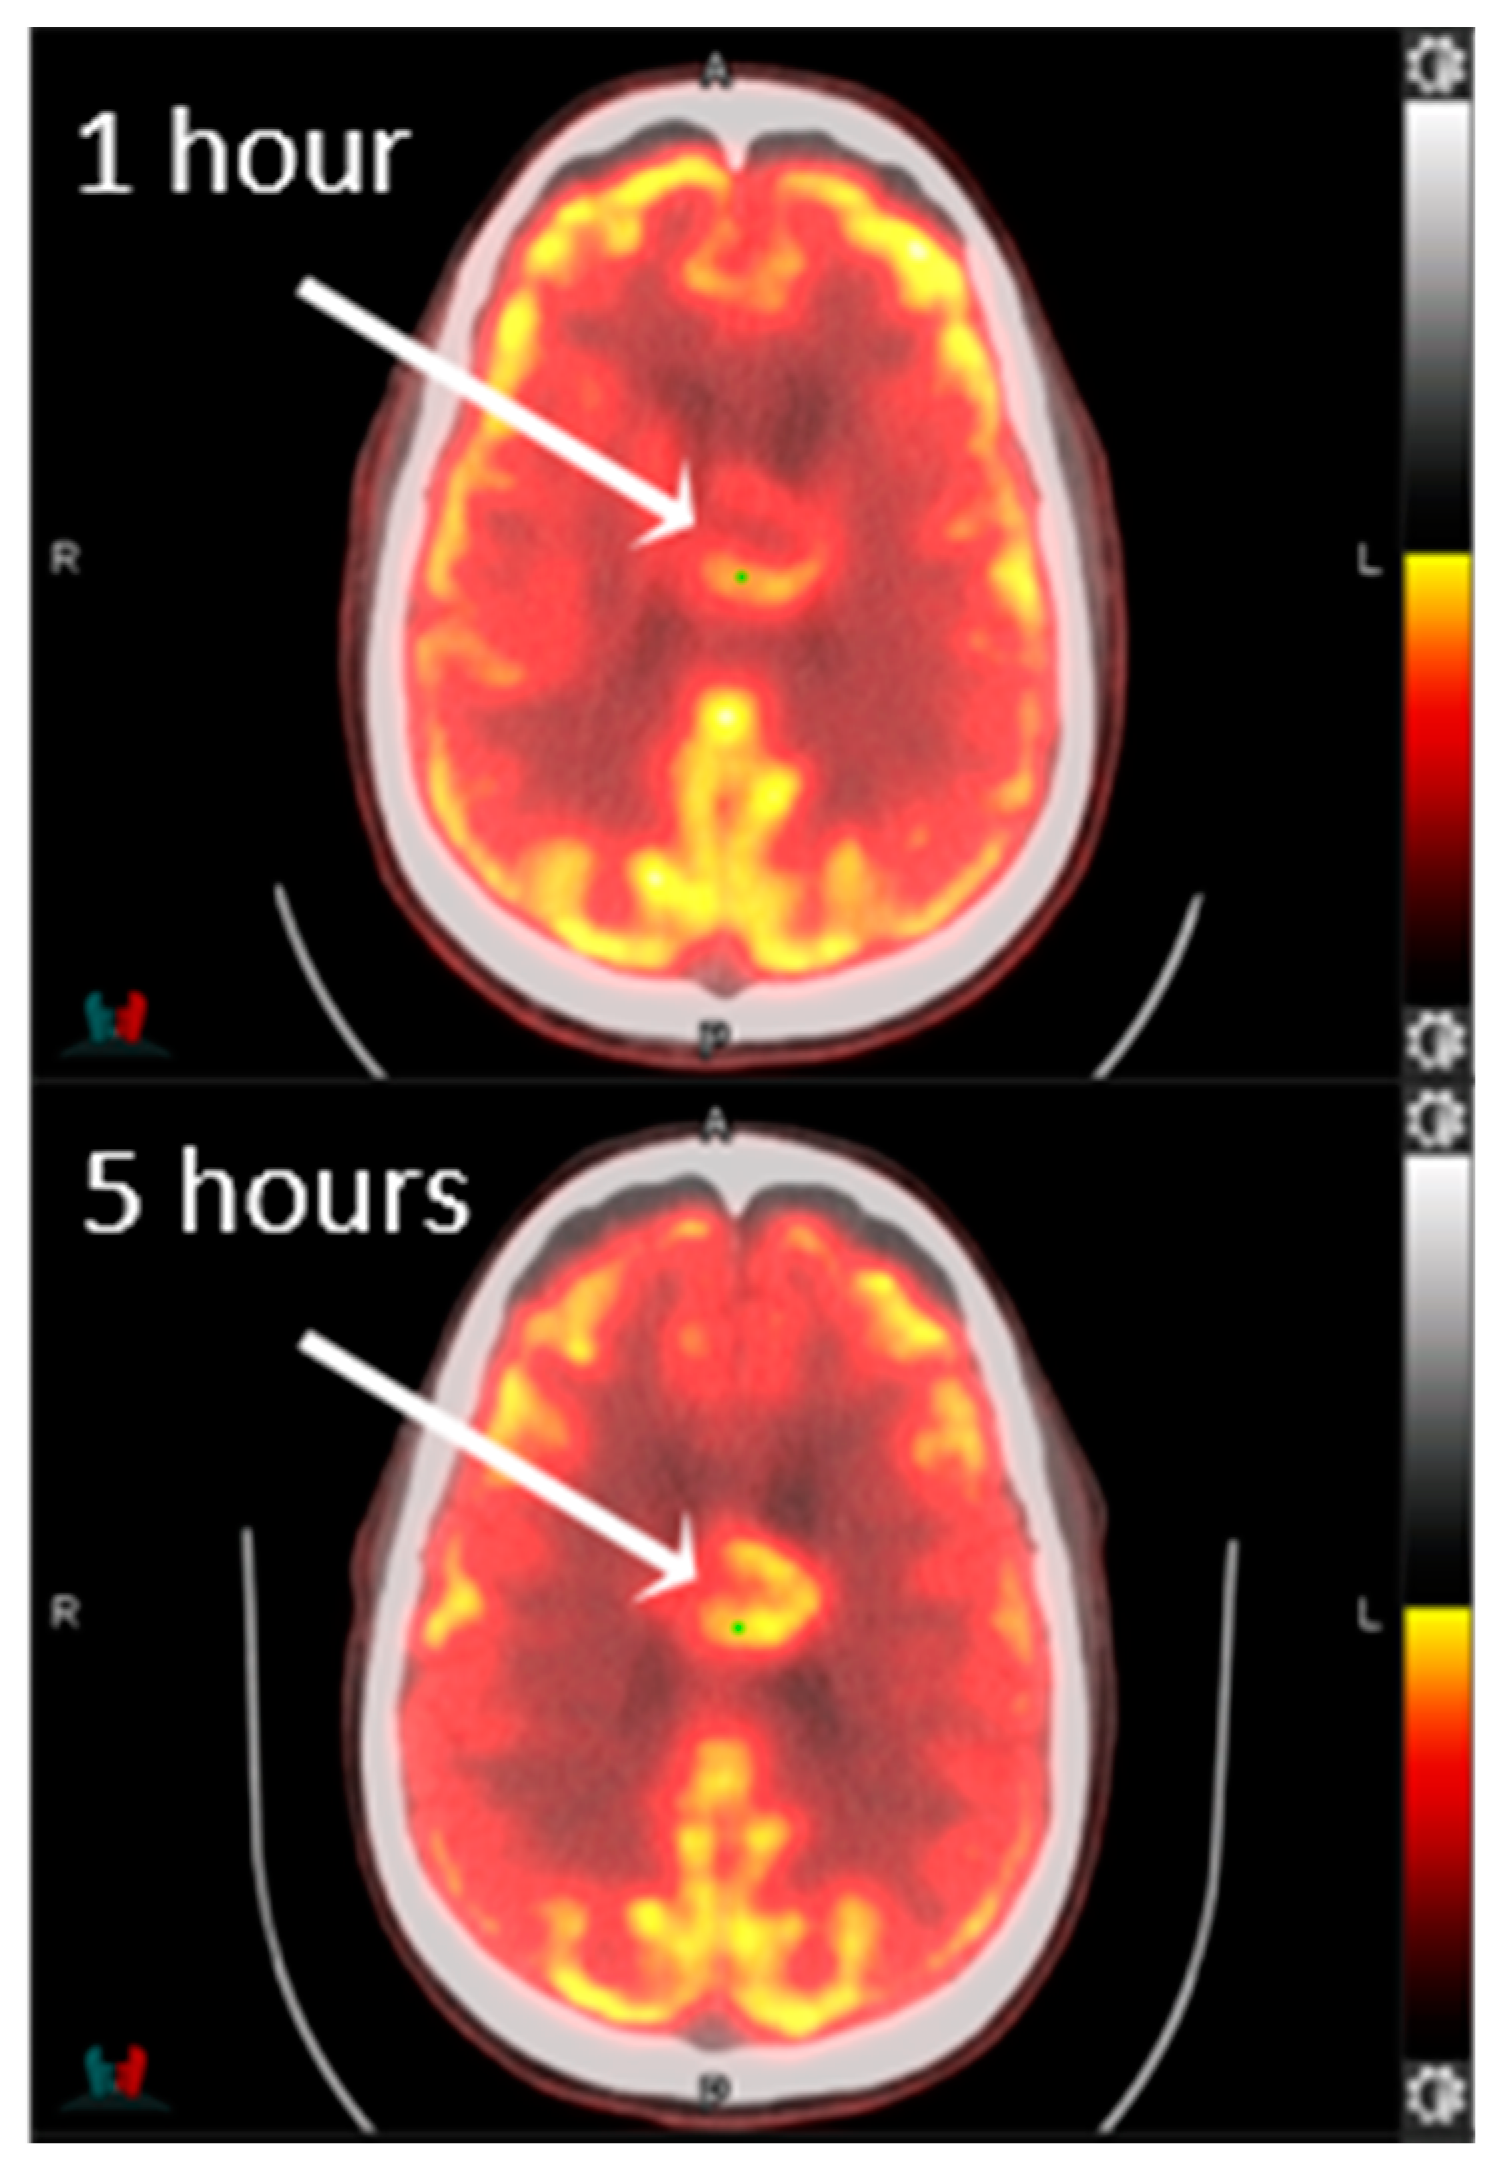

- Johnson, J.M.; Chen, M.M.; Rohren, E.M.; Prabhu, S.; Chasen, B.; Mawlawi, O.; Liu, H.L.; Gule-Monroe, M.K. Delayed FDG PET Provides Superior Glioblastoma Conspicuity Compared to Conventional Image Timing. Front. Neurol. 2021, 12, 740280. [Google Scholar] [CrossRef]